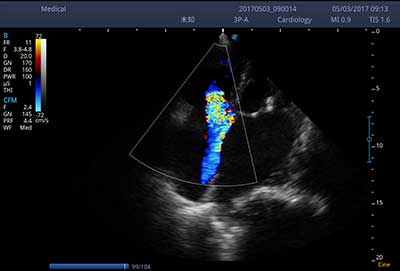

E3便携式彩色多普勒超声诊断系统拥有专业超声技术平台、高度集成化的硬件模块和结构设计、简便的操作流程、支持三探头接口全激活,兼顾了优质图像、轻便机身以及台便两用的临床使用需求。无论在常规超声科门诊检查,还是在急诊、麻醉、ICU、户外等各种应用场景。都能给您带来流程的操作体验。

频谱自动包络

一键自动优化